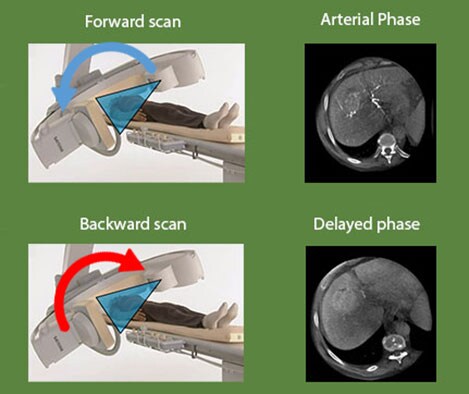

XperCT DUAL cone-beam CT to visualize both the tumor and the feeder vessels

XperCT DUAL provides imaging with almost MRI-like lesion detection. Automatic acquisition of forward and backward scans allows you to visualize the arterial phase, when the contrast agent highlights the vasculature, and the delayed phase, when the contrast agent accumulates in the tumor. Merging these two images in the DualView mode shows both the tumor and its feeder vessels.

Dr. Geschwind says: “The specific role of Dual-Phase cone-beam CT is to improve visualization of tumors, particularly in the liver. Especially for tumors that are less hypervascular, it can be very difficult to identify them and visualize them during the procedure. Obviously, if you can't see the tumor you are about to treat, you may not only miss it altogether but you may also target a large area that could result in destruction of healthy liver tissue.”